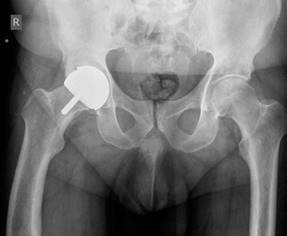

Structured Hip Oral Examination Question 2 EXAMINER : This is an anteroposterior (AP) radiograph of a 52-year…